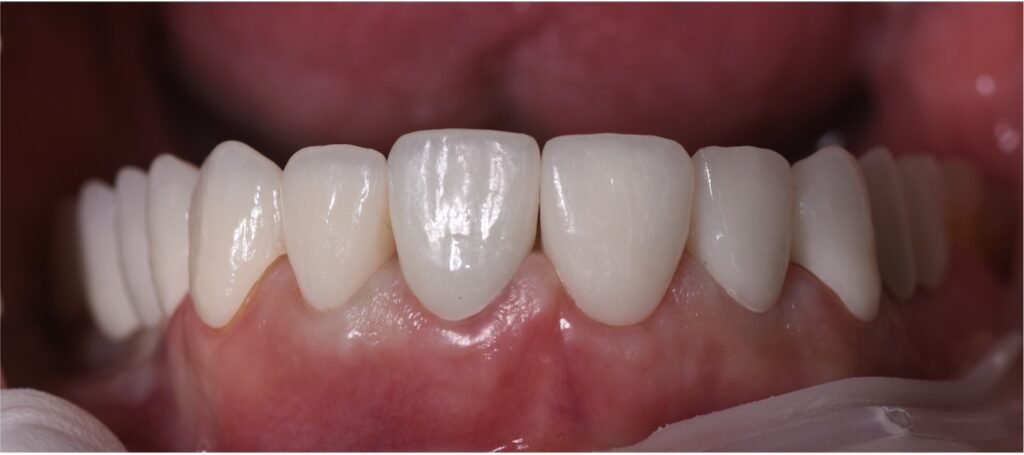

Final Outcome

The outcome of the treatment was a significant transformation in the patient's smile. The excessive gingival display was successfully reduced, and the teeth were restored to natural proportions, resulting in a more confident and attractive appearance. The patient expressed a high level of satisfaction and comfort with the result. Final photographs showed harmonious integration between teeth, gums, and facial esthetics. The patient received comprehensive instructions on hygiene and maintenance to ensure the longevity of the results.